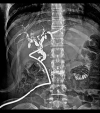

BACKGROUND Hydatid disease is a common parasitic infection in many areas of Asia, South America, and Africa. It can affect any organ, most commonly the liver. The hydatid is often asymptomatic and the diagnosis is made when complications arise. The most common complication of this disease is opening in the bile ducts, which is a life-threatening condition causing serious acute cholangitis. We report a case of acute cholangitis caused by hydatid cyst rupture into the right bile duct. CASE REPORT A 33-year-old woman, with no medical or surgical history, presented to our Emergency Department with abdominal pain, jaundice, and fever for 3 days prior to admission. The patient was hemodynamically stable. In the examination, we noticed right upper-quadrant tenderness with guarding, icterus sclera, and negative Murphy sign. A CT scan showed a liver hydatid cyst of the 4th and 8th of segments, with intrahepatic and extrahepatic biliary duct dilation. The cyst communicated with the right hepatic bile duct via a large fistula. A diagnosis of acute cholangitis was made and she underwent conservative treatment with external drainage of the pericystic cavity through the biliary duct. The postoperative course was uncomplicated and she was discharged 15 days later. CONCLUSIONS The surgical approach to hepatic hydatid must be customized based on the specific characteristics of the cyst and associated complications. Acute hydatid cholangitis is a rare but serious complication of a hydatid cyst, which requires early diagnosis and adequate surgical management.